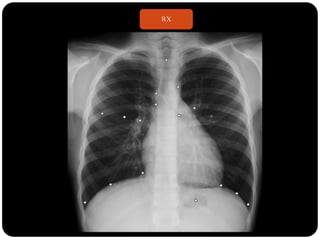

 RX

RX